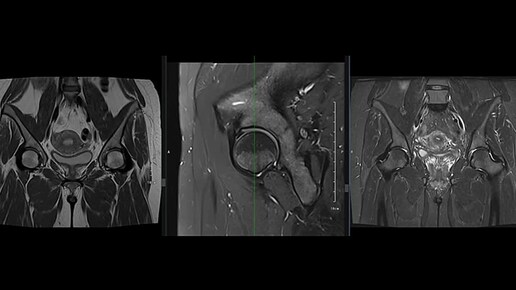

МРТ тазобедренных суставов